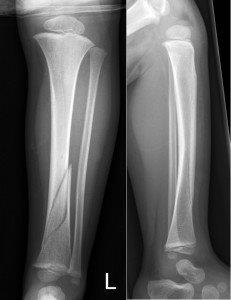

Oblique comminuted fracture of tibia and fibula

Completely displaced tibial shaft and fibula fracture from a quad bike accident. A high risk of compartment syndrome.